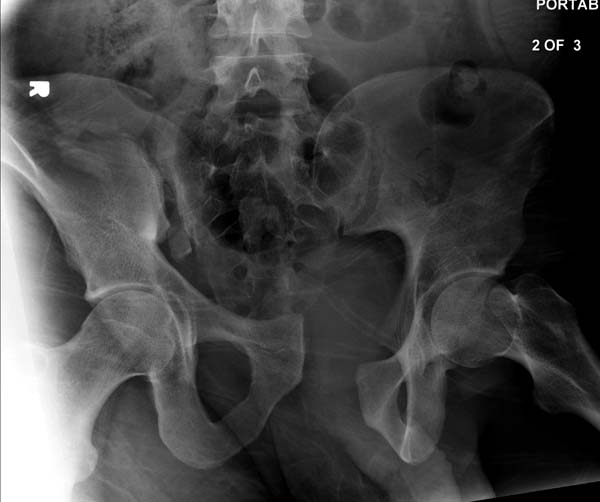

> /“При поступлении обследована (обзорный таза + вход в таз)”/

До операции желательно выставить все стандартные снимки: обзорный таза,

вход + выход. А популярный у всех 3Д используется только для общего

Перелом заднего отдела крыла подвдошной кости доказывает, что задние

связочные элементы подвздошно- крестцового сочленения интактны, и такой

перелом известен как“Сrescent fracture’. Переломы разделяется на 4 типа,

Здесь примеры фиксации с различными вариантами.... .